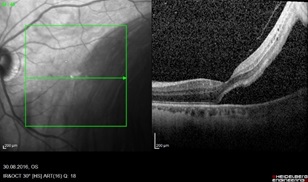

Витрэктомия при отслойке сетчатки

Если осветить глаз изнутри, то просто так ничего увидеть будет невозможно. Поэтому для получения изображения используются сложные оптические системы линз, встроенные в головы современных микроскопов, а также специальные съемные оптические системы. Они дают прекрасный обзор, независимо от рефракции пациента, позволяют работать бесконтактно и с высоким увеличением.

В суперсовременные микроскопы встроены оптические томографы, чтобы не только видеть, но и получать оптические среды маловидимых структур – все это для повышения точности и контроля ручной работы витреоретинального хирурга.

Вся работа выполняется через зрачок, поэтому чем лучше он расширяется – тем больше обзор при работе хирурга. Роговица и хрусталик также должны быть прозрачны – иначе вся картинка будет смазана. Вот почему витреоретинальные операции часто сочетают с хирургией хрусталика – в том числе для улучшения условий для осмотра глазного дна. При непрозрачных средах можно использовать эндоскопы.